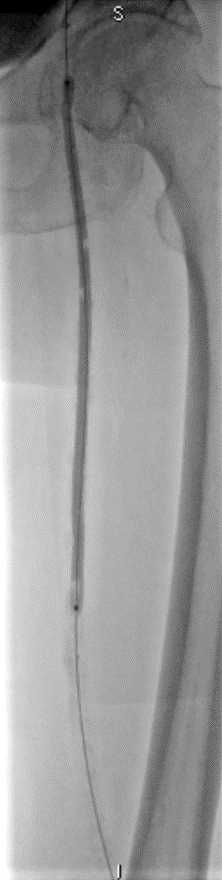

开通:以内膜下技术为主,逆穿是常用且有效的辅助手段。

预扩:充分预扩张至关重要,需逐级使用高压球囊,最终达到 6mm 直径,以获得足够的管腔。

支架植入:遵循“由远及近”原则,先放置远端 DES,再覆盖中段 VB,最后处理近端。利用 Eluvia 的可调节性优化重叠。

后扩:常规使用 6mm 高压球囊进行后扩张,确保支架充分贴壁和管腔获得。